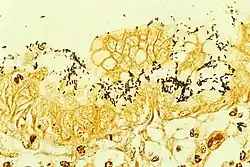

H. pylori can be demonstrated in tissue by Gram stain, Giemsa stain, H&E stain, Warthin-Starry silver stain, acridine orange stain, and phase-contrast microscopy. It is capable of forming biofilms. Biofilms hinder the action of antibiotics and can contribute to treatment failure.[34][35]